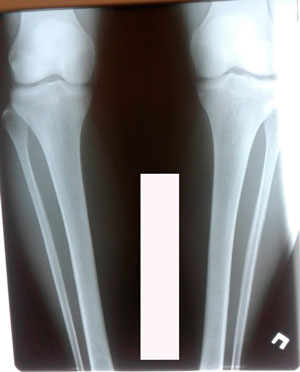

Исходник - 40 лет.

Дата операции - 09.06.2020

1,5 месяца после снятия аппаратов.